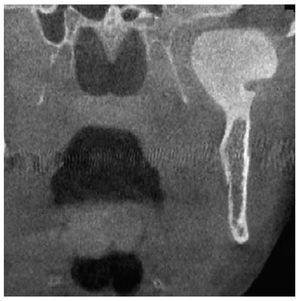

La radiografía panorámica (fig. 1) mostró una estructura de tejido óseo, densa, homogénea, con forma de hongo, bordes bien definidos y un diámetro de varios centímetros. La lesión parecía originarse en un área por encima del agujero mandibular. Un TAC de haz de cono (figs. 2 a 5) reveló la presencia de una lesión homogénea osteodensa de 3 x 3 x 2,7 cm que crecía a partir de un pedúnculo en la cara lingual de la escotadura mandibular. La circunferencia anterior alcanzaba casi a la apófisis coronoides.

Figura 3. Imagen coronal de un TAC de haz de cono.